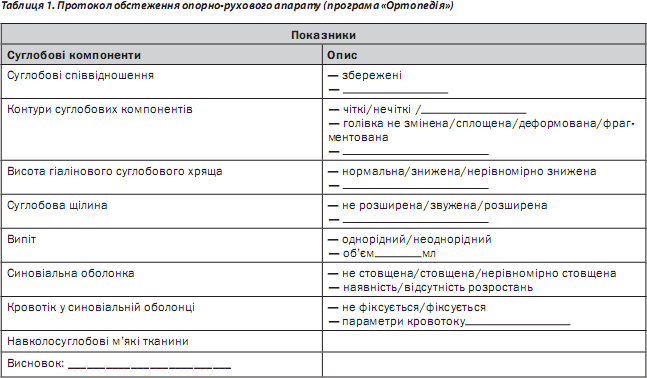

Згідно з методикою оцінюють кісткові суглобові поверхні (зміни поверхні субхондральної кістки — наявність кіст, ерозій, інших дефектів), синовіальні щілини, СО, навколосуглобові м’які тканини, наявність випоту, кровотоку в СО, зміни зв’язкового апарату тощо. Загальний протокол УЗ-обстеження хворого на ревматичні захворювання суглобів (РЗС), розроблений авторами, наведено в табл. 1.